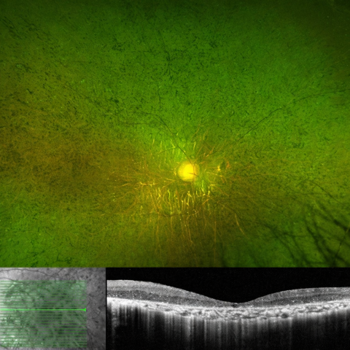

Fig 4. Optos photos of the optic nerves of a patient with optic atrophy due to a pathogenic variant in the OPA1 gene, showing bitemporal disc pallor (above) and corresponding inferotemporal retinal nerve fibre layer thinning (below). This patient is eligible for the Myrtle PYC-001 trial

Fig 5. Optos photo and OCT of the fundus of a patient with advanced rod-cone retinal dystrophy and counting-fingers vision. The OCT shows loss of photoreceptors, but preservation of the inner retinal layers, including the retinal nerve fibre layer, which is the target for KIO-301 optogenetic therapy